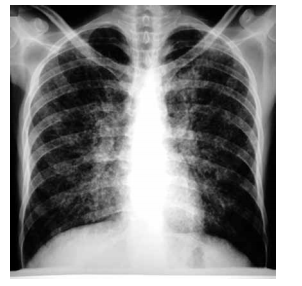

Paciente do sexo masculino, 44 anos de idade, apresenta quadro progressivo de febre vespertina, falta de ar, tosse não produtiva e desconforto torácico há 1 semana. Nega uso de medicamentos ou patologias prévias, mas relata que há 3-4 meses vem se sentindo mal, perde quase 10 kg de peso no período. Refere relações sexuais não protegidas frequentemente. Exame físico: PA: 105 x 65 mmHg, FC: 122 bpm, FR: 26 ipm, SatO2 : 79%, temperatura: 38,9 ºC; lesões orais esbranquiçadas sugestivas de candidíase. Radiografia de tórax é mostrada a seguir. Exames séricos: teste rápido para HIV: positivo; hemoglobina: 12,3 g/dL, leucócitos: 4560/mm3 e plaquetas: 165000/mm3 ; desidrogenase lática: 2740 U/L; creatinina: 0,9 mg/dL; função hepática: normal. Gasometria arterial: PaO2 : 53 mmHg.